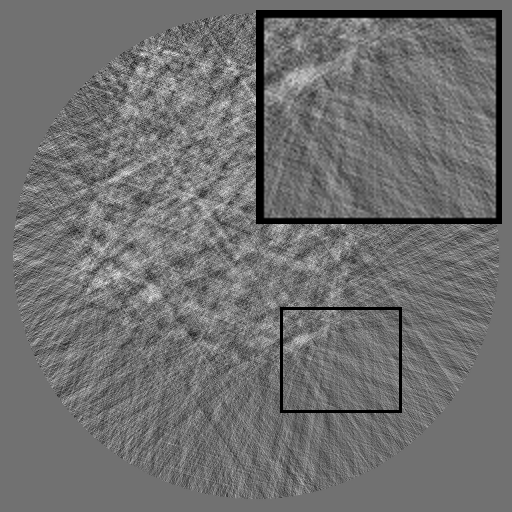

As shown in Fig 2, HRSino builds upon RePaint (Lugmayr et al., 2022) as its default backbone and restructures the inference process into a three-stage resolution-guided pipeline. The sinogram is first denoised at low resolution to establish global structure, then refined at mid resolution, and finally completed at full resolution through patch-wise inference. At each stage, the upsampled output from the previous resolution is fused with the current input before denoising, ensuring hierarchical guidance across scales. This hierarchical design avoids full-frame activation and substantially reduces memory usage while preserving long-range consistency. To further improve efficiency under the structural characteristics of sinograms, HRSino introduces two inference-time modules: (1) frequency-aware patch skipping, which exploits the spectral sparsity of background regions to bypass redundant computation, and (2) structure-adaptive step allocation, which leverages local structural heterogeneity to adjust denoising depth per patch.

Refer to caption

Figure 2: Overview of HRSino. The left illustrates the three-stage resolution-guided pipeline: low resolution followed by mid and high resolutions in a progressive refinement scheme, with the final stage performed patch-wise for detail recovery. At each stage, the upsampled output from the previous resolution is fused with the current input before denoising. The right zooms into the high-resolution stage, where two modules are applied: frequency-aware patch skipping (bypassing low-information patches) and structure-adaptive step allocation (assigning variable denoising steps by patch complexity).